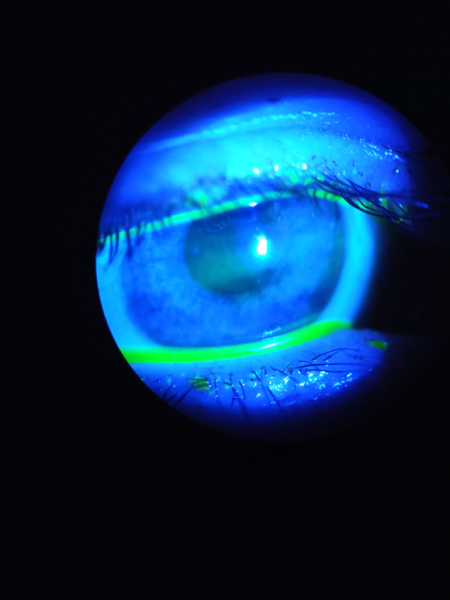

Узкий мениск Проба Норна (время разрыва слёзной плёнки): сажаем пациента за щелевую лампу, красим его глаз флуоресцеином, просим моргнуть и не моргать и смотрим, через сколько у нас пойдут разрывы в слёзной плёнке.